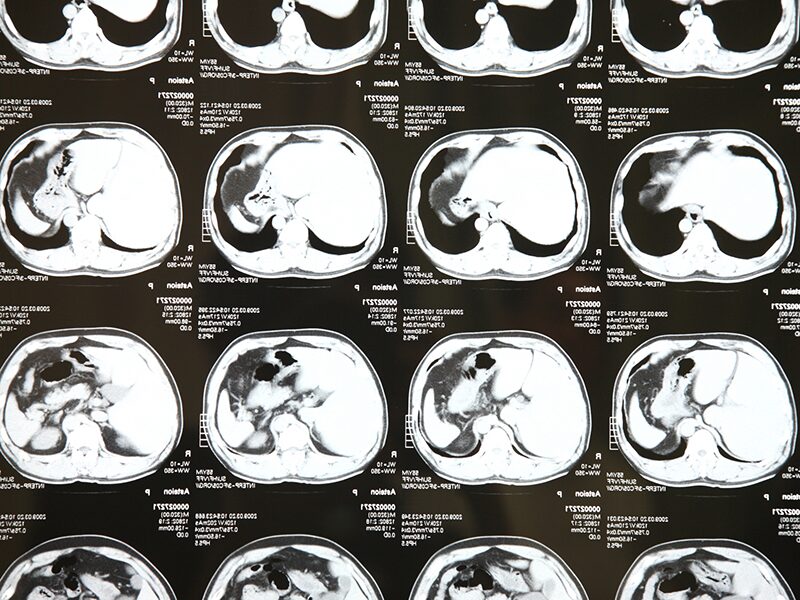

CT検査

必要に応じて、詳しい評価が必要な場合に検討します。